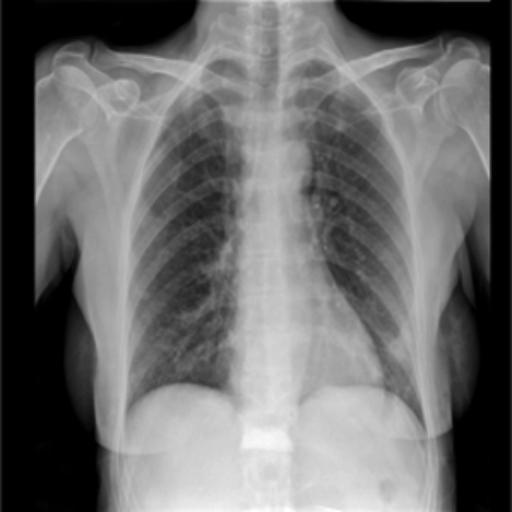

The dataset chosen in this paper is an open-source dataset, the dataset is selected from the open-source database, the database contains 150 lung X-ray images and their corresponding 150 masks, and we select four of them for presentation, the results are shown as follows, the four images in the first row are the original images of the lung X-ray, and the images in the second row in the corresponding position are their corresponding masks, as shown in Fig. 1.

Figure 1. Partial data.